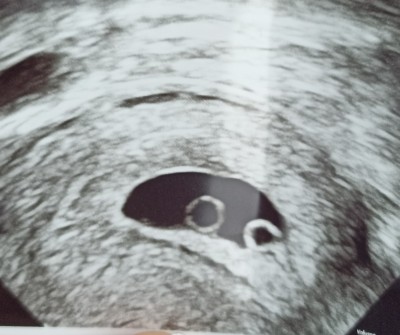

Doktor hicbirsey demeden başka doktora sevk etti 4 5hafatlik dendi sadece sizce iki kese mi var

Gebelik haftası 5

2 kese var eger kanama alani degilse tabi

Bakın burada 2 kese var elinizdeki ultrason görüntüsü ile karşılaştırabilirsiniz